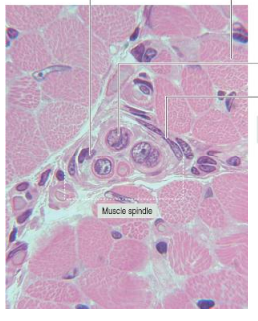

What is depicted in the image

Muscle spindle

Lec 6, Slide 16